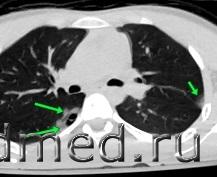

На представленных СК-томограммах на электронном носителе органов грудной полости пациента А №4473 от 23.09.20254 года, №4478 от 24.09.20254 года, №4511 от 28.09.20254 года - визуализируется перелом средней трети левой ключицы по типу «зеленой веточки», без смещения отломков, без признаков консолидации. В грудине дифференцируются зоны роста. Данных за перелом грудины, ребер, грудных позвонков не выявлено. Легкие по всем полям с обеих сторон прилежат к грудной клетке. Данных за пневмоторакс не выявлено. Бронхо-сосудистый рисунок несколько усилен. В задне-медианных отделах S6 правого легкого, на уровне тел позвонков Th5-Th8, на фоне обширной зоны контузии легкого примерным размером до 58х52х20 мм визуализируются две воздушные полости неправильной овальной формы, размером до 26х14х6 мм и до 12х10х3 мм. Полости с небольшими уровнями гетерогенного жидкостного содержимого (кровь). В правом легком: в прикорневой зоне, в S8, S9 визуализируется до 5 очагов контузии легкого по типу «матового стекла» размером от 12х10 мм до 20х15 мм. В левом легком: в S1\S2, в S4 визуализируются до 3 очагов контузии легкого по типу «матового стекла» размером от 11х10 мм до 14х9 мм. Диафрагма обычно расположена. В полости перикарда и в плевральных полостях свободной жидкости не выявлено. Заключение: КТ-картина участков разрыва правого легкого в задне-медианных отделах S6; разнокалиберных зон ушиба в обоих легких. Перелом с\3 левой ключицы без смещения. Травматические изменения могут соответствовать сроку травмы в ДТП от 23.09.2025 года

Картинки от рентгенолога

Рентгенолог физически не может видеть разрушение структур такой толщины т.к. толщина срезов не может быть менее 0,5мм, на практике же при исследовании грудной клетки в 80% толщину среза устанавливают 1-1,5мм. Кроме того, если есть травматический "разрыв" легкого, должно быть и кровоизлияние в окружающие ткани, на снимках его нет. Я уже не говорю, что за т.н. разрыв можно запросто принять междолевой промежуток с элементами плеврита.... Я бы на такой диагноз, тем более выставленный рентгенологом, не судебником, не повелся... у нас еще и не такое напишут...